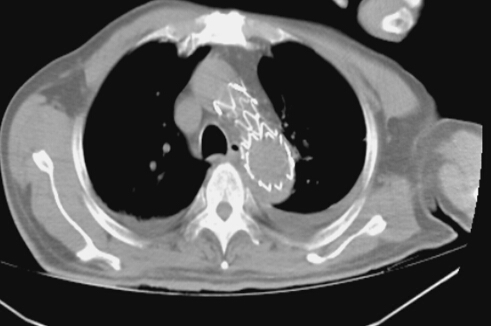

術后見支架位置良好,將破口隔絕,胸腔積液明顯減少

各相關科室醫(yī)護人員迅速準備到位,成立搶救小組,各司其職。鄭翼德主任在大血管介入治療方面有著豐富的經驗,搶救小組經過仔細討論研究,決定對患者實施胸主動脈帶膜支架腔內隔絕術。緊急氣管插管、麻醉、股動脈切開、主動脈造影,一切都有條不紊地進行。透視監(jiān)視下,導絲導管從股動脈進入,向上“游”走到升動脈弓處,造影明確夾層破口位置及撕裂情況,選取適當支架系統(tǒng),在支架穩(wěn)穩(wěn)妥妥地放入預定主動脈內后,再次造影顯示破口完全封堵,未見經內漏繼續(xù)出血,手術取得圓滿成功。大家雖然苦了、累了,汗流浹背,卻個個露出了開心的笑容。